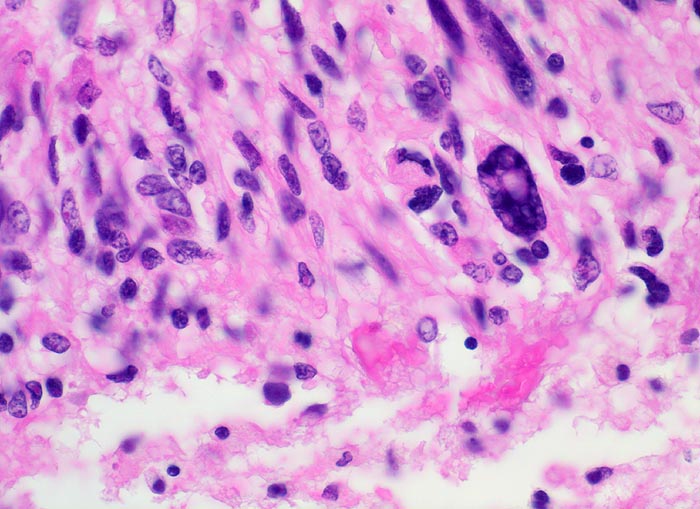

Morphologische Merkmale:

• Zellreicher Tumor mit sehr unscharfer Begrenzung zum normalen Hirnparenchym (rechts unten).

• Typische streifenförmige Nekrosen mit randständiger Palisadierung der Tumorzellen.

• Im Zentrum der Nekrose thrombosierte Gefässe umgeben von einem Saum vitaler Tumorzellen.

• Pathologische glomerulumartige zellreiche Gefässknäuel.

• Ausgeprägte Zellpolymorphie und Atypie.

• Mitosen.